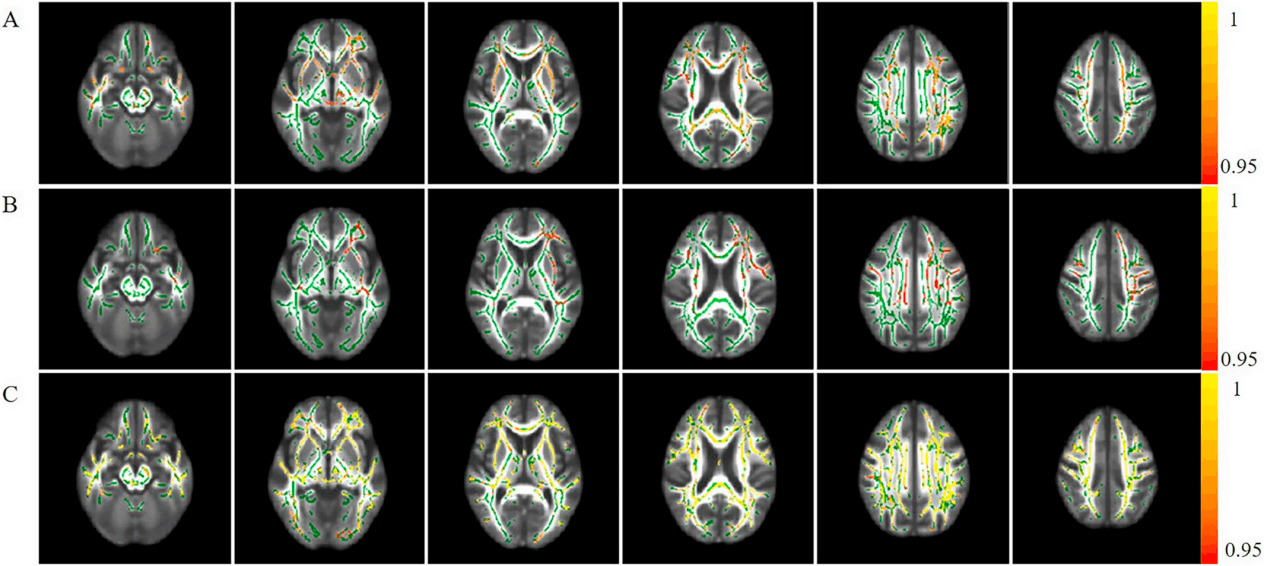

NODDI数据分析系统采用多室模型来解析水分子扩散信号,旨在提供更具生物学特异性的微结构指标。该系统通过算法将体素内的信号分解为细胞内、细胞外及脑脊液三个成分,从而定量估计神经突的密度与方向分散度。这超越了传统扩散张量指标,能更特异性地反映在脑发育、老化及多种神经精神疾病中发生的神经突改变,为理解白质微观结构的生物学基础提供了独特视角。